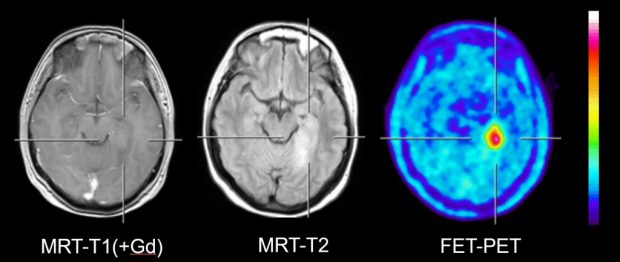

Hirntumore und deren Ausdehnung lassen sich mit einem Verfahren namens Positronen-Emissionen-Tomographie (PET) hochpräzise erkennen. Nach jahrzehntelanger Arbeit am Forschungzentrum Jülich (FZJ) bei Aachen hat der Gemeinsame Bundesausschuss, das höchste Beschlussgremium der gemeinsamen Selbstverwaltung im deutschen Gesundheitswesen, jetzt beschlossen, dass die Kosten für eine PET-Untersuchung von den Krankenkassen getragen wird. Dem für die Diagnose nötigen Radiopharmakon [18F]-Fluorethyltyrosin (FET) fehlt allerdings noch die arzneimittelrechtliche Zulassung, sodass PET vorerst nur in spezialisierten Zentren angewendet werden darf. Bild: Forschungszentrum Jülich Tumore leuchten in rot und gelb FET wird vor der Untersuchung in die Blutbahn gespritzt. Es sammelt sich bevorzug in Tumorzellen an. Es emittiert Positronen, das sind elektrisch positiv geladene Elementarteilchen, praktisch die Gegenstücke von Elektronen. Wenn FET gespritzt ist dauert es ein wenig, bis es dort angekommen ist, wo es hinsoll. Es sendet Positronen aus, die von einer Spezialkamera aufgefangen werden, die auf den Kopf des Patienten gerichtet ist. Tumore leuchten auf diesen Bildern leuchtend rot/gelb auf. Auf Aufnahmen von Magnetresonanztomographen sind solche Tumore kaum auszumachen. Das Verfahren lässt sich nicht nur nutzen, um anfänglichen Krebsbefall und die Ausdehnung des Tumors zu erfassen, sondern auch in der Nachsorge, etwa während und nach einer Strahlentherapie. Dann kann man sehen, wie die Therapie anschlägt und ob nach dem Ende der Behandlung noch Reste des Tumors vorhanden sind, die möglicherweise auf andere Art bekämpft werden können. Klarheit über Erfolg oder Misserfolg Die radioaktiv markierte Aminosäure FET wurde in den Neunzigerjahren im FZJ-Institut für Nuklearchemie entwickelt. „Unser Team hat in Kooperation mit den Universitätskliniken in Aachen, Bonn, Köln und Düsseldorf inzwischen mehr als 170 experimentelle und klinische Studien über dieses Verfahren publiziert und über 8000 Patienten mit Hirntumoren untersucht“, so Professor Karl-Josef Langen, der maßgeblich an der Entwicklung beteiligt war. Einzugsgebiet von 300 Kilometern Inzwischen greifen Fachärzte aus einem Umkreis von mehr als 300 Kilometern auf die Expertise des Jülicher Instituts beziehungsweise der Nuklearmedizinischen Klinik des Universitätsklinikums Aachen zurück. Die aktuellen Forschungsarbeiten konzentrieren sich darauf, die die PET-Diagnostik mit der Hochfeld-Magnetresonanztomographie zu kombinieren, um die Aussagekraft weiter zu steigern. via Forschungszentrum Jülich Teile den Artikel oder unterstütze uns mit einer Spende. Facebook Facebook Twitter Twitter WhatsApp WhatsApp Email E-Mail Newsletter